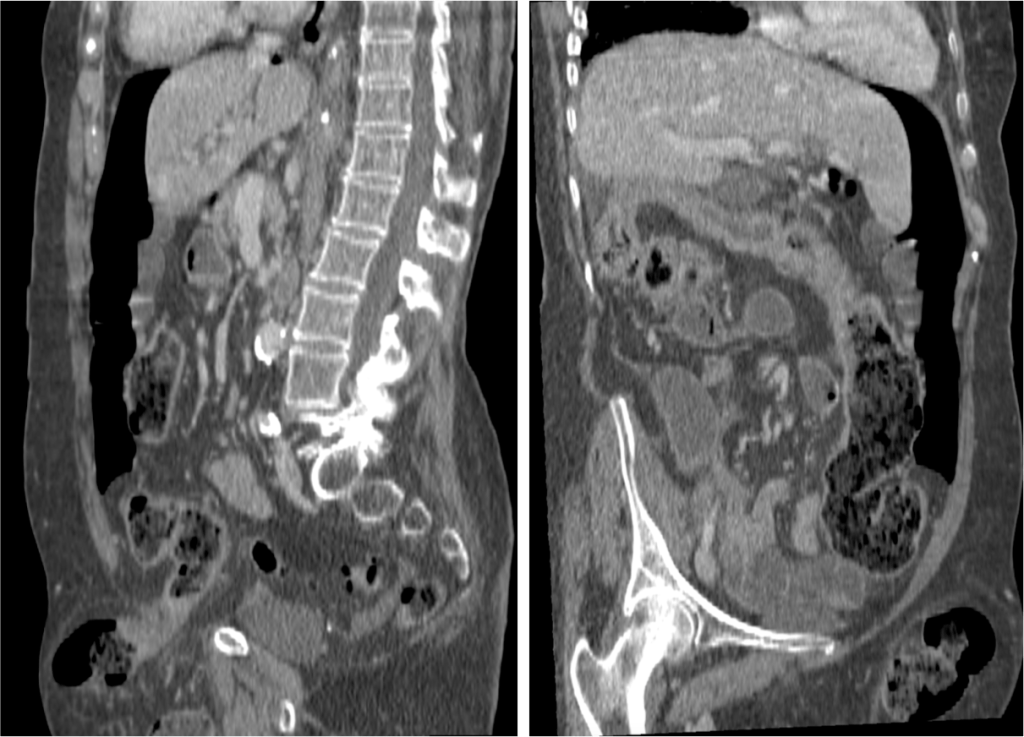

Normalmente se forman en el estómago de pacientes con historia personal previa de cirugía gástrica o enfermedad psiquiátrica. Los bezoares pueden darse en el estómago, intestino delgado o intestino grueso y pueden presentarse aislados y ser múltiples.

Pacientes jóvenes entre 15 – 19 años. Pueden asociar enfermedad psiquiátrica o antecedes de cirugía gástrica. Síntomas: indigestión/malestar estomacal, dolor, náuseas, vómitos, diarrea, anorexia, pérdida de peso, úlceras gástricas, obstrucción intestinal

- CT abdominal: Es la prueba de elección.

- Masa con baja densidad intraluminal + patrón de burbujas de aire moteado ( patrón característico).

- Edema de pared y engrosamiento de mucosa.

- Obstrucción intestinal: cambios de calibre y dilatación de asas pre estenosis. El CT puede determinar la causa, localización y grado de obstrucción intstinal.

- Sd de Rapunzel: cola de pelo que se extiende desde el estómago al intestino y puede producir obstrucción.

- Perforación: líquido libre y neumoperitoneo.

- El CT puede ayudar a distinguir entre un bezoar y particulas de comida. Los bezoares son redondos u ovoides, flotan en la superficie de agua/aire rodeados del contenido gástrico y que además muestran menor densidad que las partículas de comida. Los bezoares grandes tienden a rellenar todo el lumen y muestran burbujas distribuidas en el intersticio de la masa. Sin embargo, en ocasiones puede ser dificil difrenciar un bezoar de un cantidad considerable de comida retenida o de las heces si se localizan en el colon. Un hallazgo que puede ayudarnos, es identificar que dicha masa esta produciendo una obstrucción.

- La ventana estándar abdominal de (level, 40 H; width, 350 H) puede hacer muy dificil el diagnóstico de bezoar. Es recomendable bajar el Nivel/Level de la ventana hasta los L -1oo H o jugar con dichos niveles hasta identificar mejor las características del bezoar.